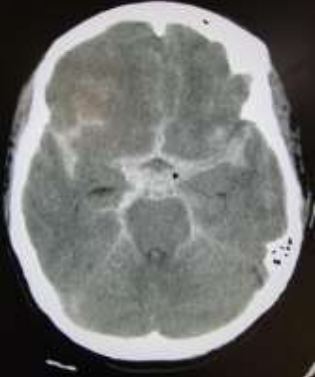

Paciente do sexo masculino, 50 anos, hipertenso não controlado, dá entrada em serviço de emergência hospitalar com quadro de cefaleia súbita aguda e rebaixamento do nível de consciência. A TC de crânio realizada na unidade demonstra o seguinte achado:

Sobre este caso, assinale a alternativa correta.